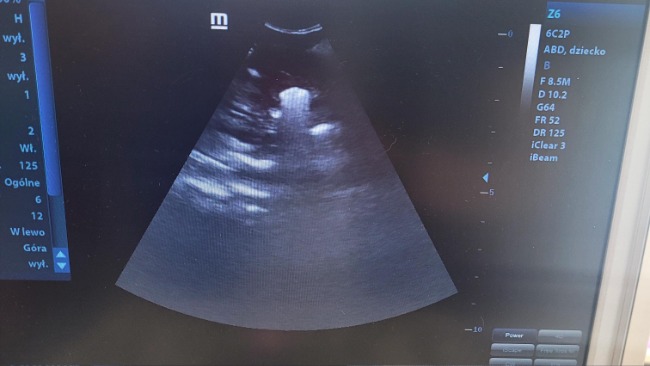

Badania były tylko formalnością, która potwierdziła diagnozę jakiej się spodziewałam, a usg pokazało ogrom zbierającego się płynu w brzuszku